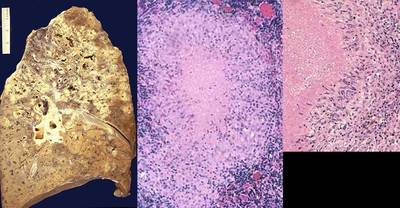

What type of necrosis is demonstrated in these images?

Answer

• Gangrenous

• Coagulative

• Fat

• Caseous

What is the type of necrosis demonstrated by these images?

• Liquefactive